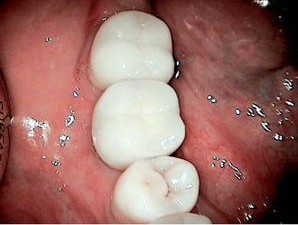

As the primary dental care provider, the general dentist is perfectly positioned to not only make the diagnosis, but to educate and treat the patient to completion. Once the treatment has been accepted, the hopeless root (with no ferrule) is atraumatically extracted. If both the buccal and lingual walls remain intact, simple socket preservation techniques can be utilized so that in three to four months the general dentist now has “created” an optimal implant site. If pathology or less than traumatic extraction leaves you with a compromised buccal or lingual boney plate, then socket augmentation is performed, and an optimal implant site is available for implant placement in four to five months.

There is no better way to care for our patients than by creating implant-ready sites by treatment of a patient’s emergent need. As patients in my Expanded Services Dental Practice have found, dental implants now are a very realistic tooth replacement option for them. Through my own education, as well as the education of my Team and my patients, implants have become not only a regular topic of discussion in my office, but also a regular course of treatment for my patients. In the next issue of Sidekick, you can read my article discussing “The “Cents” of Implants for The General Practitioner,” i.e., the financial impact of the above-mentioned techniques on your bottom line.